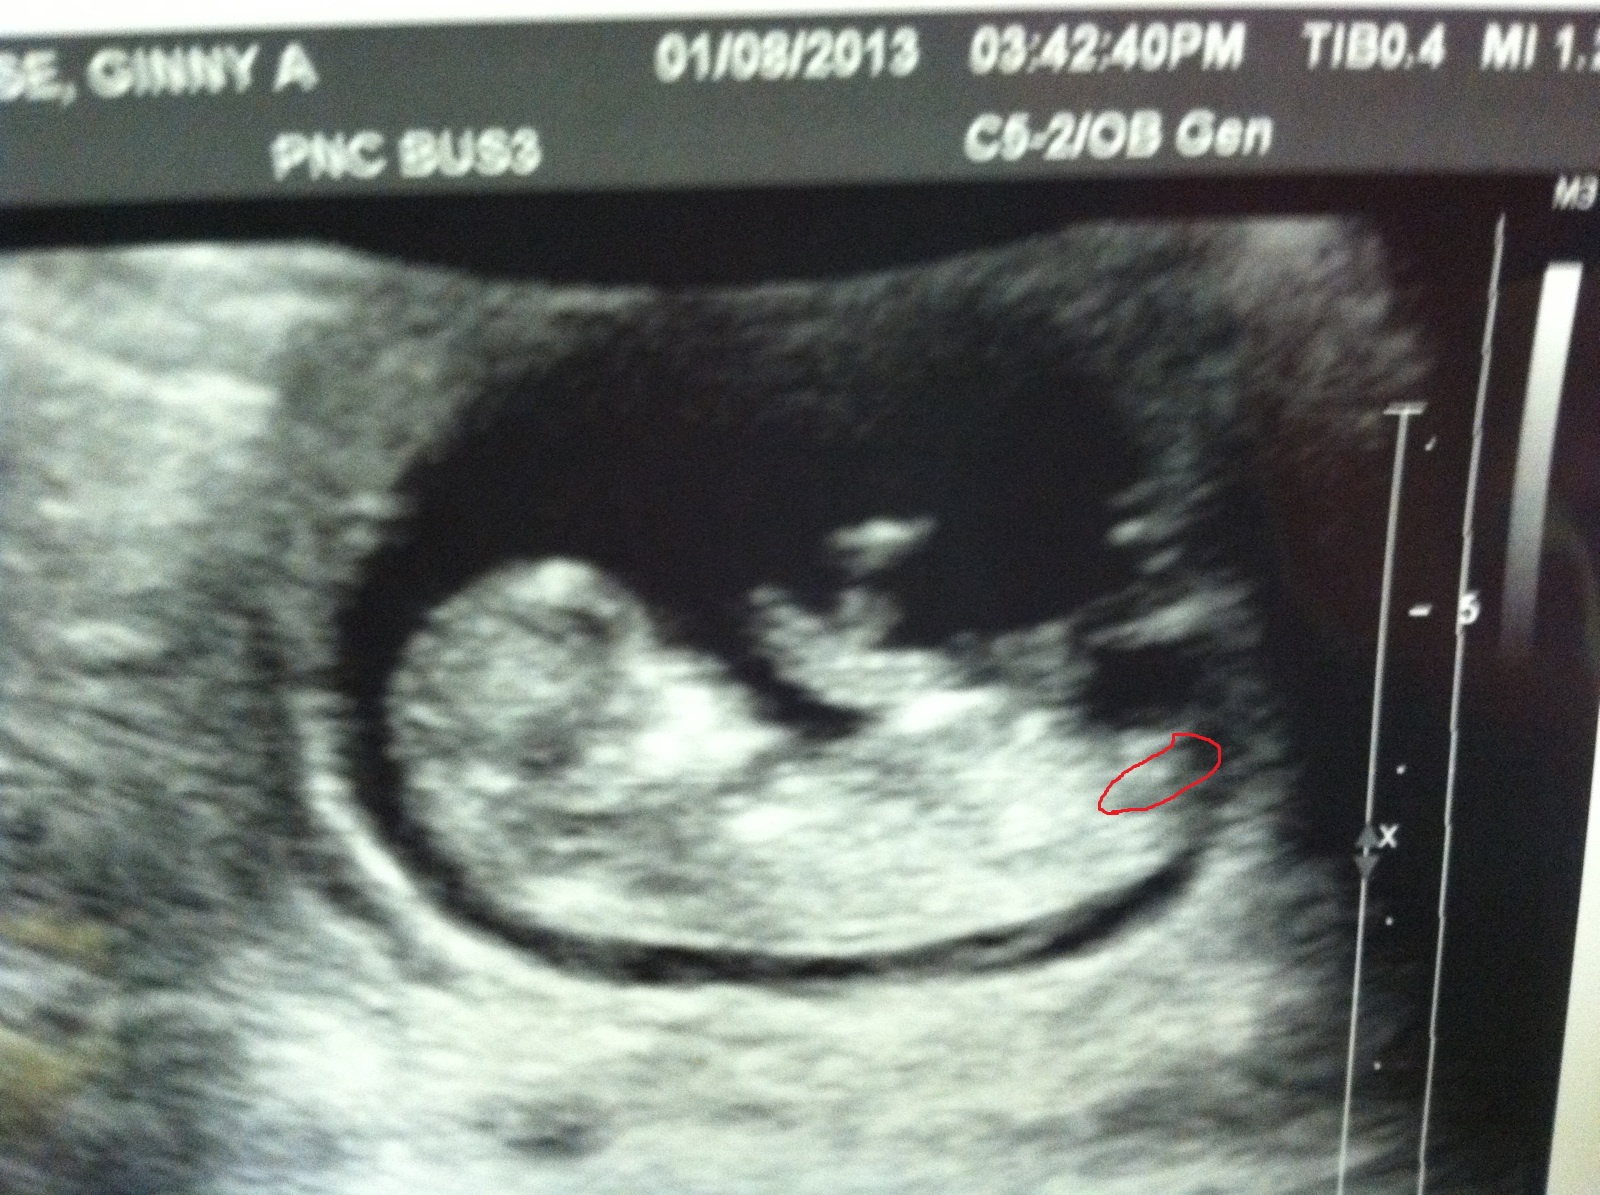

Ladies, am I not seeing the nub correctly? I circled what I think is it, and I'm not convinced it looks that girly. Attachment 8462